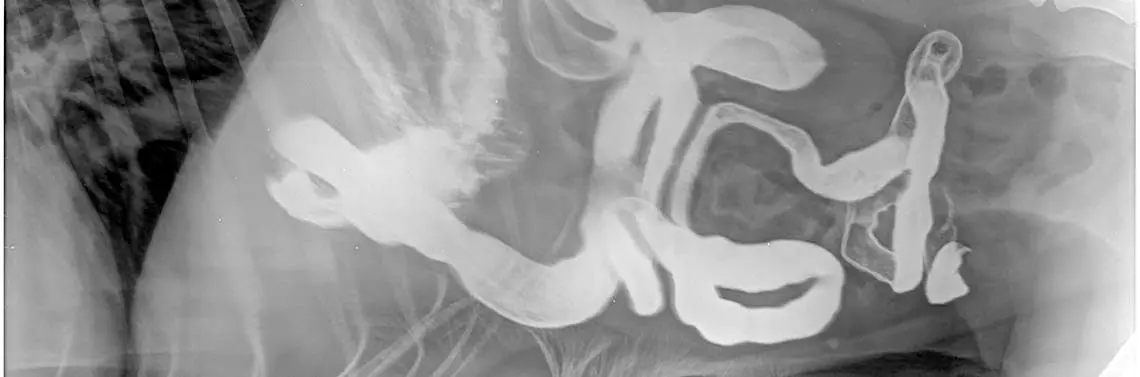

Biorąc pod uwagę wielkość cząsteczki antygenowej, tj. białko i jej połączenie z substancjami dodatkowymi, musimy liczyć na szereg sprawnych mechanizmów trawiennych odpowiadających za bezpieczny rozkład spożytego posiłku na drobne elementy, przy udziale odpowiedniej ilości m.in. śluzu, wydzieliny soków trawiennych, perystaltyki oraz m.in. odpowiedniego pH [3, 8, 13]. Nie możemy w tym wypadku nie doceniać pracy wątroby oraz wydzieliny pęcherzyka żółciowego. Nie byłoby także prawidłowego trawienia, gdyby nie działania endogenne (wydzielanie do krwioobiegu) i egzogenne (poprzez przewód wyprowadzający) wielu komórek wydzielniczych np. trzustki (fot. 3A – u kota i 3B – u psa). Tylko homeostaza pomiędzy syntezą a rozpadem, wydzielaniem a trawieniem, wchłanianiem, a wydalaniem i wieloma innymi procesami gwarantuje niezbędną równowagę [3, 5, 6, 8, 24].